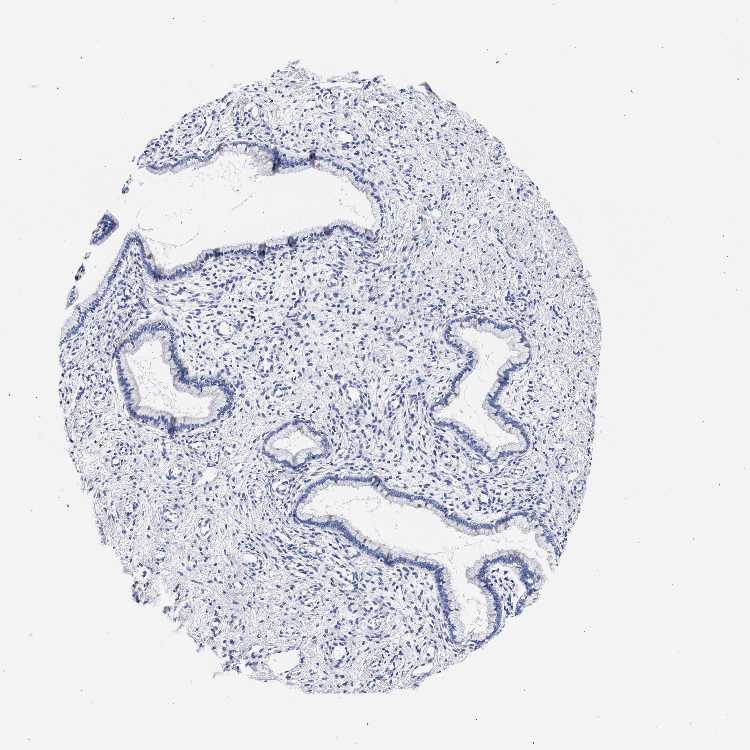

RAB3B